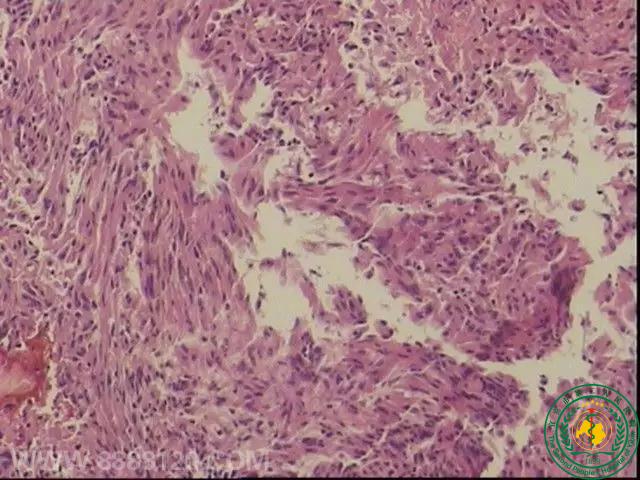

神经外一科完成四川省第一例经鼻神经内镜下蝶窦脑膜瘤切除术

神经外一科完成四川省第一例经鼻神经内镜下蝶窦脑膜瘤切除术18029